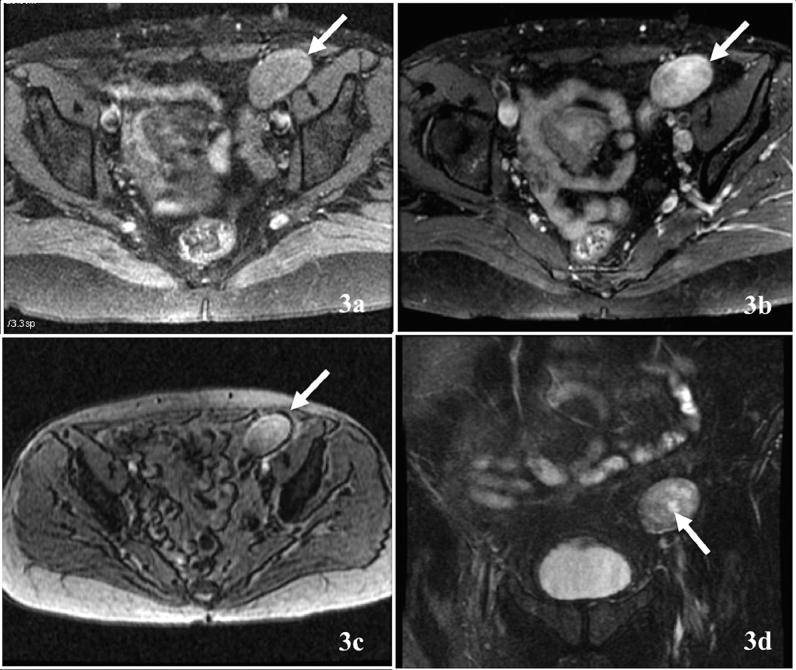

Uterine leiomyomas are one of the most common tumors affecting reproductive-age women. Leiomyomas can present as an intrauterine mass or rarely as an extrauterine tumor. Depending on its location, the diagnosis of extrauterine leiomyoma can be challenging, and multiple imaging modalities may be needed for correct identification and differentiation from malignant entities. We report the case of a 48-year-old-postmenopausal female who presented with a painful left inguinal mass, which was clinically diagnosed as inguinal hernia. Ultrasound, computed tomography, magnetic resonance imaging, and percutaneous biopsy were used to characterize the mass. Surgical resection and histopathological analysis revealed the mass to be a parasitic leiomyoma, a very rare cause of inguinal hernia, especially in a postmenopausal woman.

子宫平滑肌瘤是影响育龄女性的最常见肿瘤之一。平滑肌瘤可表现为子宫内肿物,极少情况下表现为子宫外肿瘤。根据其位置,子宫外平滑肌瘤的诊断可能具有挑战性,可能需要多种成像方式来正确识别并与恶性病变相鉴别。我们报告一例48岁绝经后女性病例,该患者出现左侧腹股沟肿物伴疼痛,临床诊断为腹股沟疝。通过超声、计算机断层扫描、磁共振成像及经皮活检对肿物进行特征性描述。手术切除及组织病理学分析显示该肿物为寄生性平滑肌瘤,这是腹股沟疝非常罕见的病因,尤其在绝经后女性中。